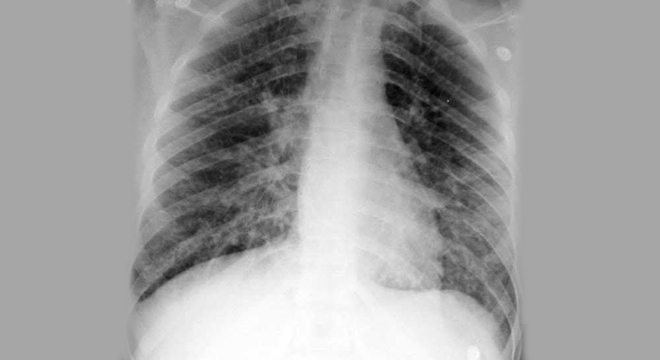

Lungenentzündung: Röntgenaufnahme der Lungen

• Röntgenaufnahmen der Lunge